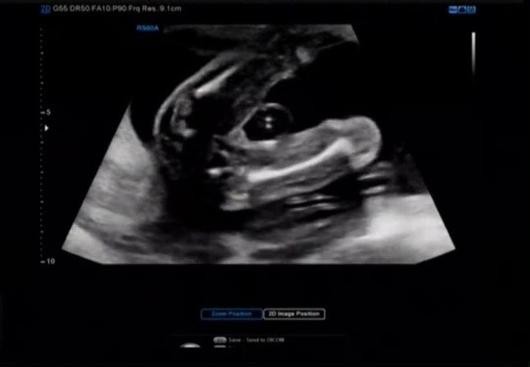

20일 김소영은 자신의 인스타그램을 통해 "어제 갑자기 컨디션이 좋지 않아 걱정하고 악몽도 꿨는데 다음날 정기검진에서 해맑게 엉덩이 자랑 중인 셜록잉"이라는 글과 함께 한 장의 사진을 게재했다.

공개된 사진 속에는 김소영의 초음파 사진이 담겨 있는 모습. 예비 엄마로서 아기에 대한 애정이 한껏 묻어나는 글 역시 훈훈함을 자아냈다.